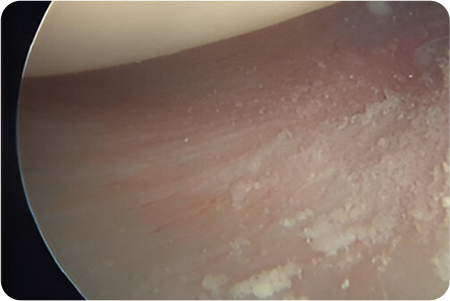

석회제거술

어깨 힘줄 조직에 석회질이 침착하여 발생하게 되는

석회성건염이 있을 때 시행하게 됩니다.

관절경을 이용해 석회주변부에서 염증이 생긴

점액낭을 제거함과 동시에 석회 침착물을 제거

합니다.